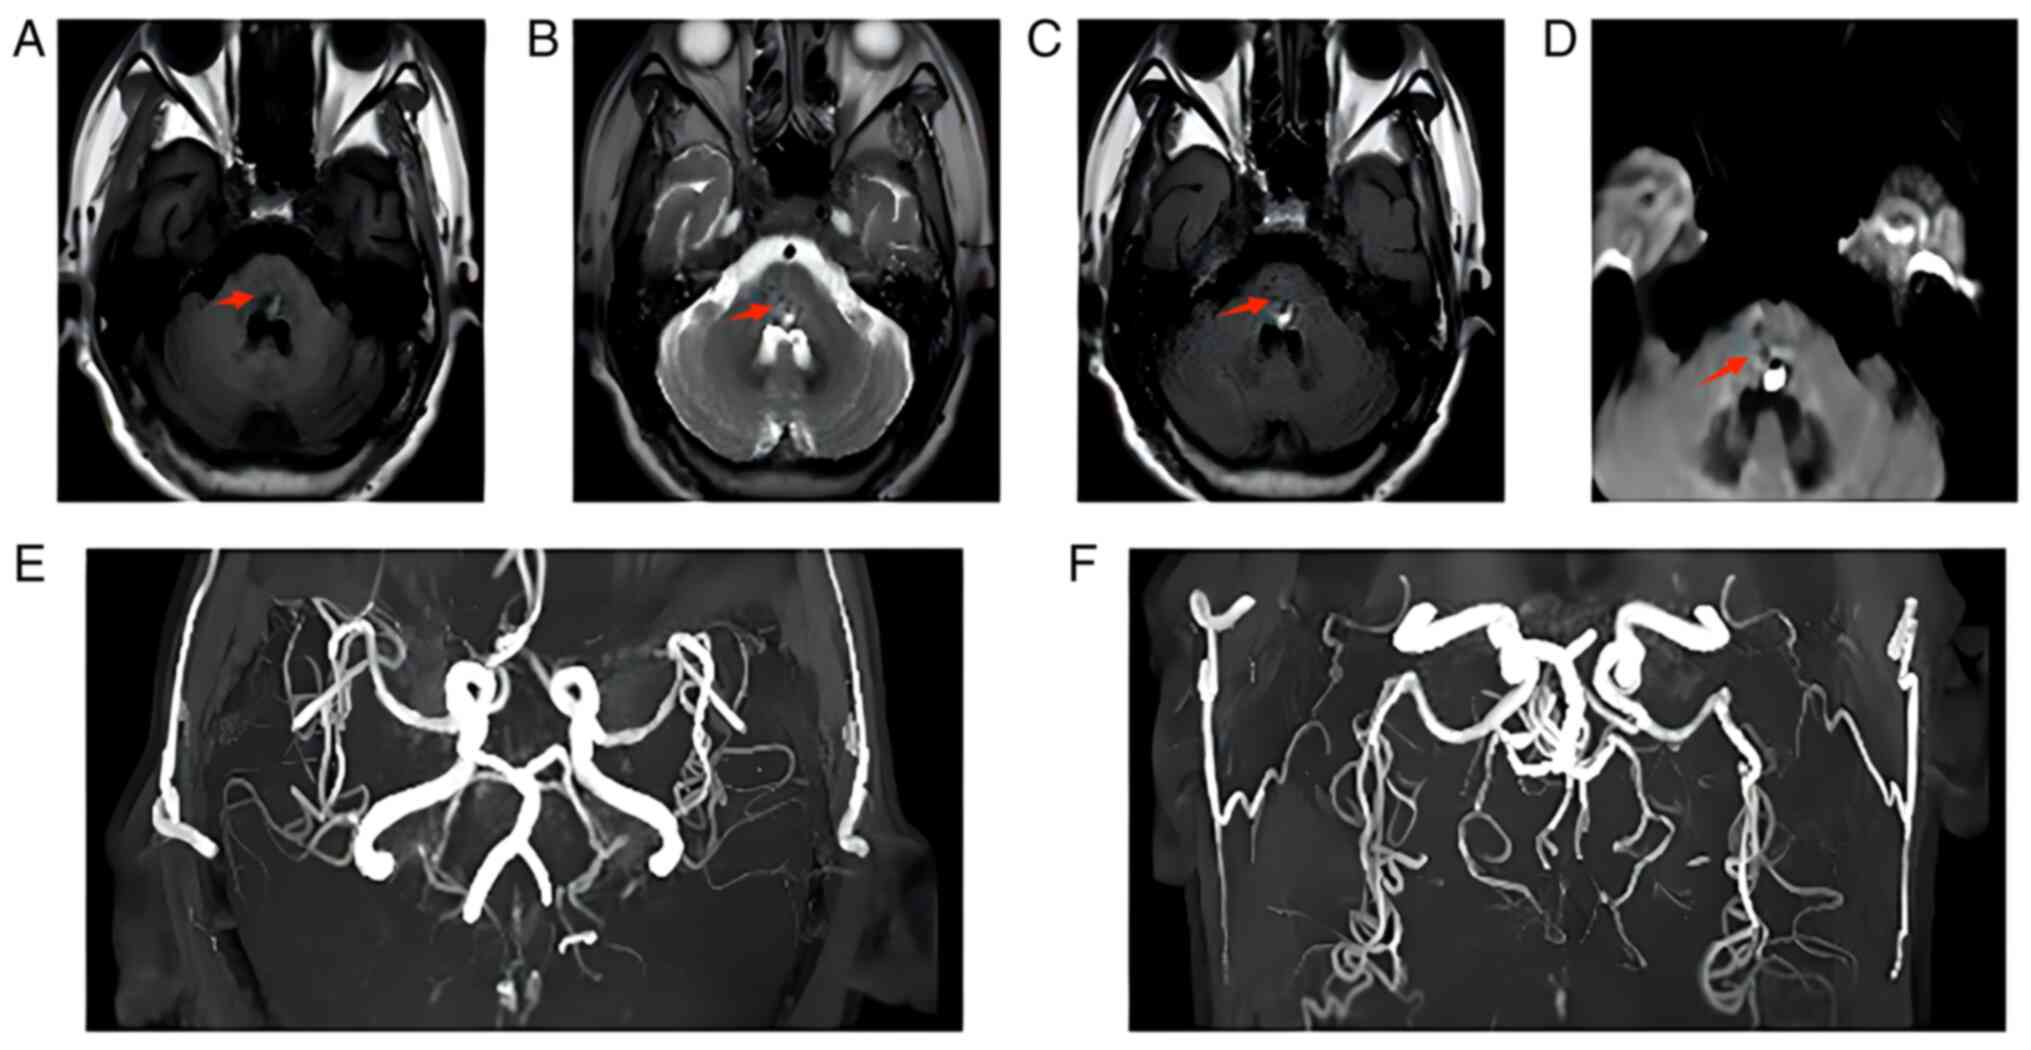

On 31st May, cranial magnetic resonance imaging and magnetic resonance angiography (Fig. 2A-F) showed dominant mixed-signal shadow in the cerebral bridge with a low signal. The left middle cerebral artery was slightly narrowed, and the posterior cerebral artery was stiffened bilaterally, which was considered cerebral arteriosclerosis. The patient still had numbness in the right limb and was then treated with rehabilitation acupuncture, which was the stimulation of specific acupuncture points along the skin of the body using thin needles. It gradually improved his numbness in the right limb, and subsequently he received regular HD.

Figure 2

Cranial magnetic resonance imaging + magnetic resonance angiography on 31st May showed a piece of (A) short T1 and (B) long T2 dominant mixed signal shadow in the cerebral bridge, surrounded by low signal. (C) fluid attenuated inversion recovery and (D) diffusion-weighted imaging showed high signal locally, and cerebral bridge haematoma was considered. (E and F) The lumen of the M1 segment of the left middle cerebral artery was slightly narrowed, and the posterior cerebral artery was stiffened bilaterally, with uneven lumen thickness and slightly reduced branches, which indicated cerebral arteriosclerosis. The red arrow shows the haemorrhage site.